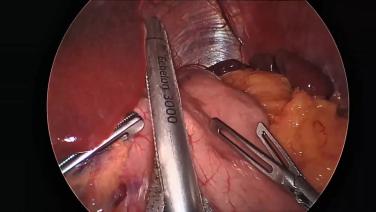

Laparoscopic Sleeve Gastrectomy Using the ENSEAL™ X1 Straight Jaw Tissue Sealer and ECHELON™ 3000 Stapler with Kelvin Higa, MD

Sleeve Gastrectomy with the ECHELON 3000 stapler and ECHELON Staple Line Reinforcement

Sleeve Gastrectomy Using the ECHELON™ 3000 stapler and ECHELON™ Staple Line Reinforcement with Dexter Turnquest, MD

Sleeve Gastrectomy with the ECHELON 3000 stapler, ECHELON Staple Line Reinforcement, and ENSEAL X1 Curved Jaw Tissue Sealer

Sleeve Gastrectomy Using HARMONIC 1100 Shears and the ECHELON 3000 with Brandon Helbling, MD

Sleeve Gastrectomy Using the ECHELON™ 3000 Stapler with Staple Line Reinforcement and Harmonic™ 1100 Shears with Betsy Dovec, MD